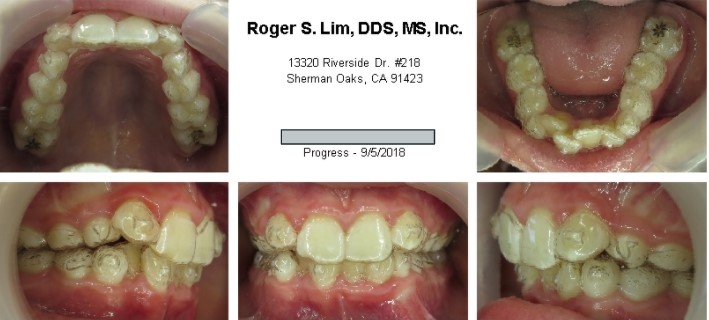

Posterior crossbite before Expander

Posterior crossbite after Expander